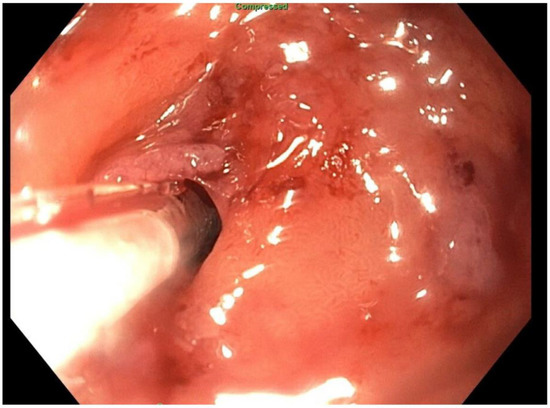

2. Detailed Case Description